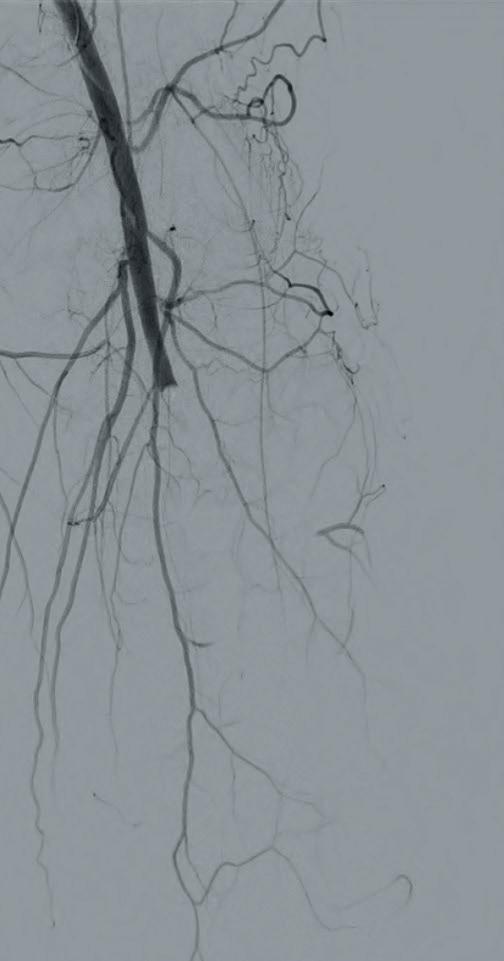

Shockwave E8 3mm x 80mm to the posterior tibial artery

The posterior tibial artery was successfully crossed first. The long-length posterior tibial artery disease was treated with a Shockwave E8 3.0mm x 80mm IVL catheter, with no pre-dilatation required. A total of 200 pulses were delivered along the length of the posterior tibial artery (Figure 3).

Shockwave E8 3mm x 80mm to the peroneal artery

Following this, the peroneal artery occlusion was successfully crossed. The longlength peroneal artery disease was treated with the same Shockwave E8 3mm x 80mm IVL catheter also with no pre-dilatation required. The remaining 200 pulses were

delivered across the length of the peroneal artery disease (Figure 3).

Left SFA intervention

To ensure adequate inline blood flow to the tibial vessels, the SFA disease was treated with drug-coated balloon angioplasty, followed by self-expanding stent placement.

Post-intervention arteriogram

An excellent technical result was achieved. The SFA was widely patent with no significant residual stenosis. The posterior tibial and peroneal arteries were widely patent with brisk flow and no residual stenosis. Significantly improved flow was identified to the foot (Figure 4).